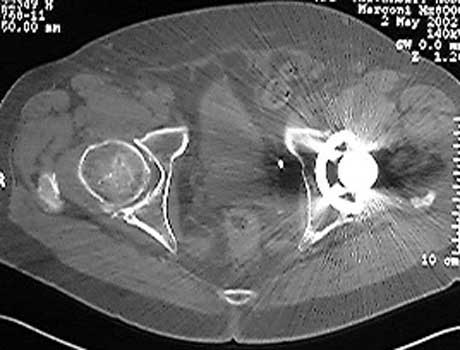

Dislocated femoral component and acetabular cup in grossly loose arthroplasty.  CT guided aspiration to rule out infection.